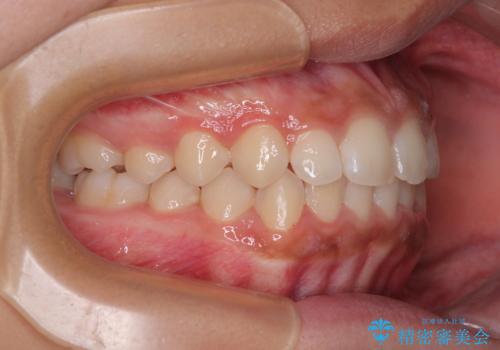

気になるすきっ歯を短期間で改善 インビザライン矯正

- 前歯の隙間を気にして来院された患者様です。

口元の突出感があり、小臼歯4本を抜歯して口元を引っ込める矯正治療も提案しましたが、本人は口元の突出感は気になっていないとのことで、インビザラインにて隙間やデコボコを改善することとしました。

軽度の歯列不正であったため、廉価版のインビザライン・モデレートパッケージにて治療を終えることができました。